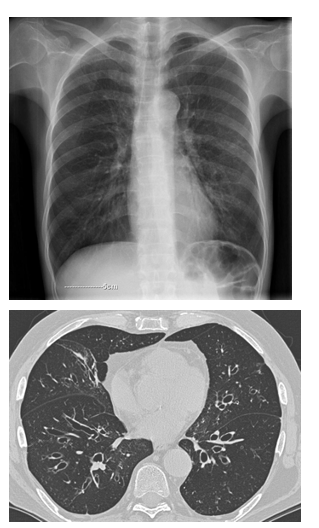

What investigations would you do for bronchiectasis?